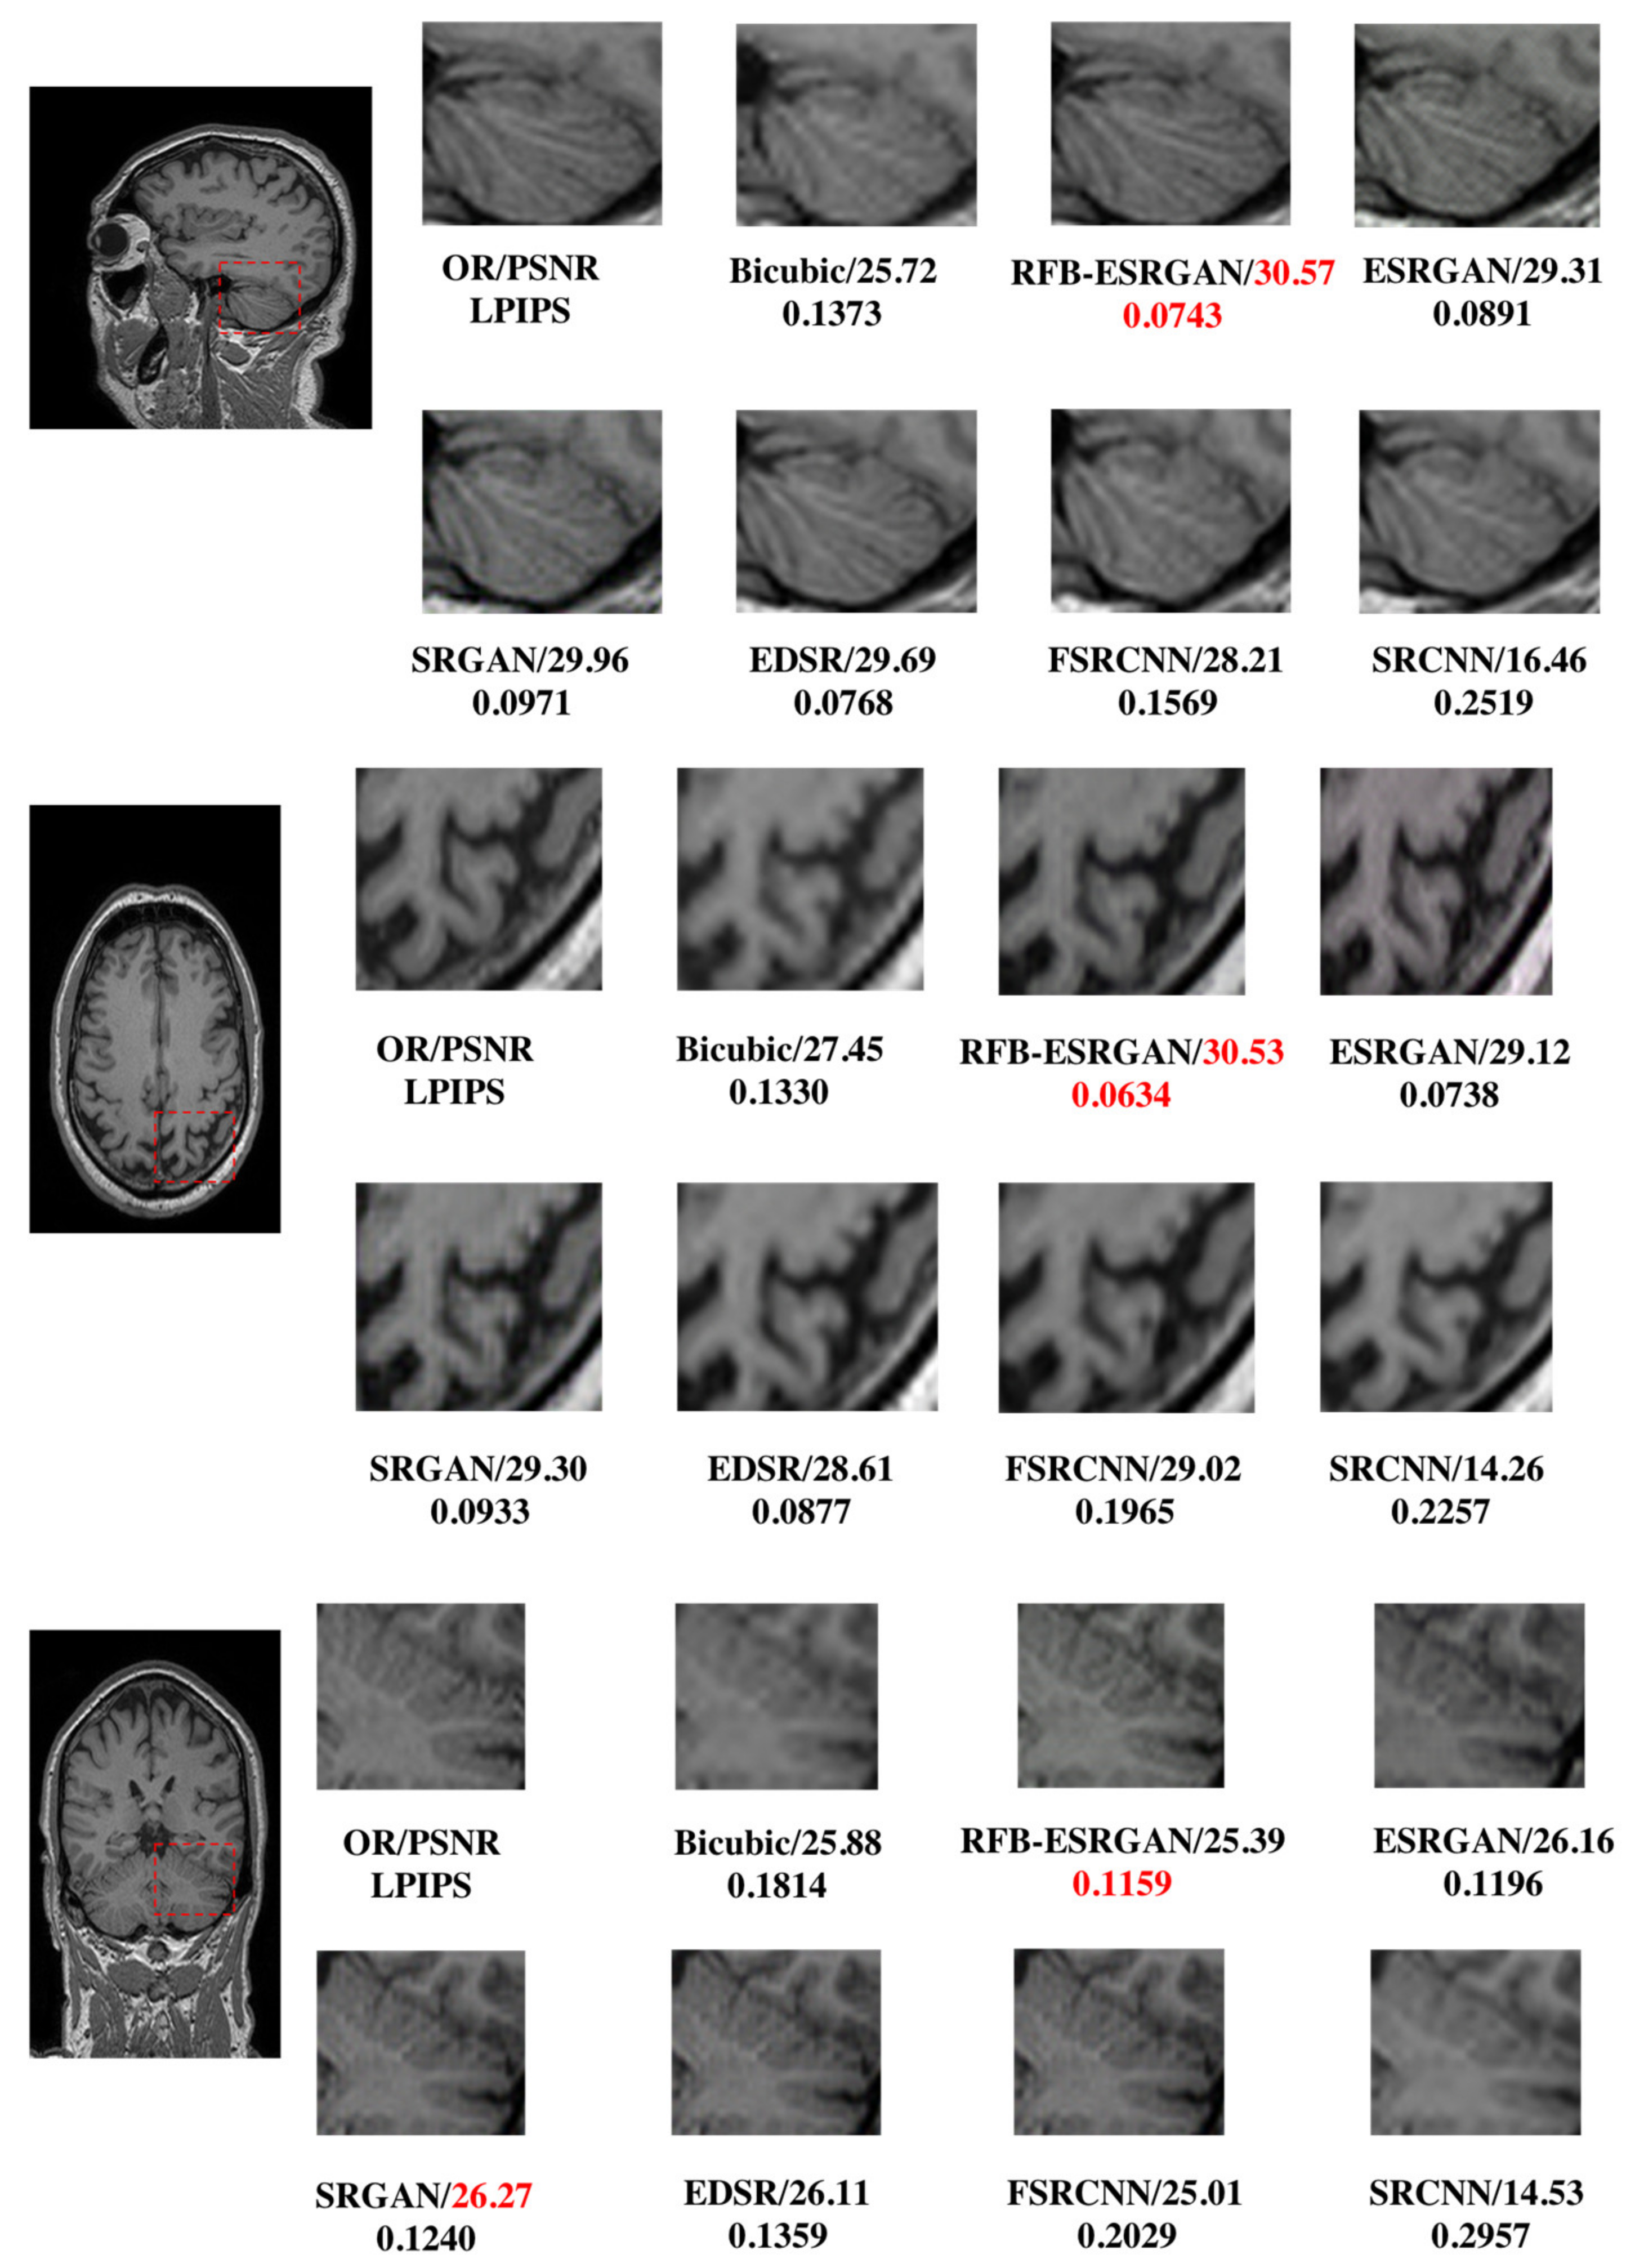

3.2.1. RFB-ESRGAN

| Plane/ Method | Evaluation | Bicubic | SRCNN | FSRCNN | EDSR | SRGAN | ESRGAN | RFB-ESRGAN |

| Sagittal | PSNR ↑ | 25.13 | 14.40 ± 0.22 | 25.77 ± 0.56 | 25.62 ± 0.31 | 26.45 ± 0.64 | 25.37 ± 0.45 | 26.20 ± 0.59 |

| SSIM ↑ | 0.8106 | 0.3196 ± 0.0095 | 0.8337 ± 0.0041 | 0.8963 ± 0.0035 | 0.8959 ± 0.0057 | 0.8856 ± 0.0054 | 0.9201 ± 0.0041 | |

| LPIPS ↓ | 0.1996 | 0.3228 ± 0.0127 | 0.2140 ± 0.0044 | 0.1501 ± 0.0043 | 0.1522 ± 0.0064 | 0.1525 ± 0.0054 | 0.1411 ± 0.0043 | |

| Coronal | PSNR ↑ | 26.95 | 14.10 ± 0.37 | 29.25 ± 0.64 | 27.70 ± 0.80 | 29.16 ± 0.79 | 29.15 ± 0.86 | 29.94 ± 0.83 |

| SSIM ↑ | 0.7491 | 0.4175 ± 0.0516 | 0.7732 ± 0.0124 | 0.9430 ± 0.0047 | 0.9372 ± 0.0067 | 0.9366 ± 0.0049 | 0.9641 ± 0.0032 | |

| LPIPS ↓ | 0.149 | 0.2411± 0.0127 | 0.1884 ± 0.0095 | 0.1006 ± 0.0087 | 0.1077 ± 0.0064 | 0.0807 ± 0.0092 | 0.0750 ± 0.0075 | |

| Axial | PSNR ↑ | 29.19 | 16.46 ± 0.44 | 28.42 ± 1.12 | 28.85 ± 1.09 | 27.69 ± 0.92 | 27.12 ± 0.88 | 30.69 ± 0.83 |

| SSIM ↑ | 0.8115 | 0.3682 ± 0.0301 | 0.8224 ± 0.0452 | 0.9417 ± 0.0056 | 0.9027 ± 0.0157 | 0.9083 ± 0.0089 | 0.9600 ± 0.0031 | |

| LPIPS ↓ | 0.131 | 0.2519 ± 0120 | 0.2035 ± 0.0174 | 0.1005 ± 0.0088 | 0.1148 ± 0.0088 | 0.1104 ± 0.0079 | 0.0839 ± 0.0074 | |